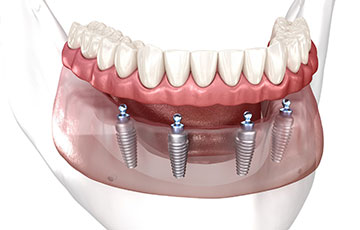

オールオン4

重度の虫歯や歯周病で歯が強く揺れている場合、無理に残しても十分に噛めないことがあります。そのようなケースでは、オールオン4が検討されます。安定した噛み心地と自然な見た目を両立でき、口腔内環境の改善につながります。

「痛い」「外れやすい」「硬い物が噛みにくい」など、総入れ歯の悩みを抱える方は少なくありません。オールオン4はインプラントでしっかり固定するため、ズレや違和感を軽減し、安心して食事や会話を楽しめます。

歯を失った期間が長いと、顎の骨は徐々に痩せていきます。オールオン4は残っている骨を活用してインプラントを配置する治療法のため、骨量が少ない方でも適応できる可能性があります。

- しっかり噛める安定感

- オールオン4は、インプラントを顎の骨に固定して人工歯を支えるため、総入れ歯と比べて高い咬合力が期待できます。硬い食材も無理なく噛めるようになり、食事の満足度や日常の快適さが大きく向上します。

- 歯を失ったままにすると顎の骨は徐々に痩せていきますが、インプラントは噛む力を骨に伝えるため、骨吸収の抑制が期待できます。オールオン4は長期経過でも骨の安定が報告されており、将来を見据えた治療法として選ばれています。